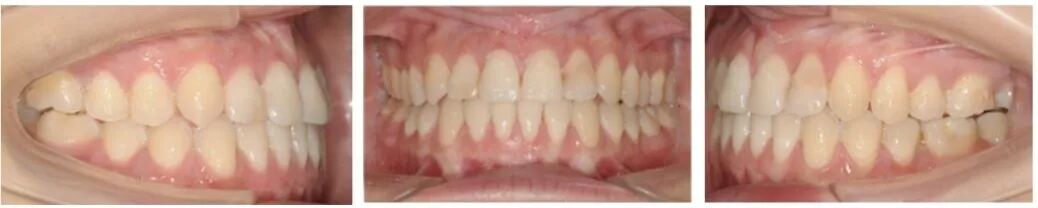

口腔检查:

上下牙弓呈方圆形;双侧尖牙、磨牙III类关系;21牙与31牙呈切合;前牙呈现约1 mm的局部开合;下颌中线较上颌中线左偏1 mm。

保持3个月的口内像,可以看到矫治效果是比较稳定的。

治疗后头影重叠图可见47牙大量前移关闭拔牙间隙,下颌前上旋转;下前牙少量伸长解决开合,下前牙少量内收、直立。